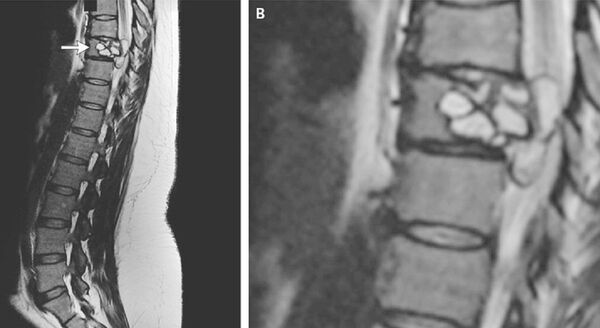

The first symptoms, like inability to stand upright and legs losing sensation, as well as preliminary blood tests pointed to some sort of infection, however an MRI gave the game away: the woman appeared to have a serious lesion in the middle part of her backbone. It was further revealed that painful “electric,” as she put it, shocks in both legs could have been caused by larval cysts from a dog tapeworm, which were spotted in the lesion that was later surgically removed and replaced with an implant.